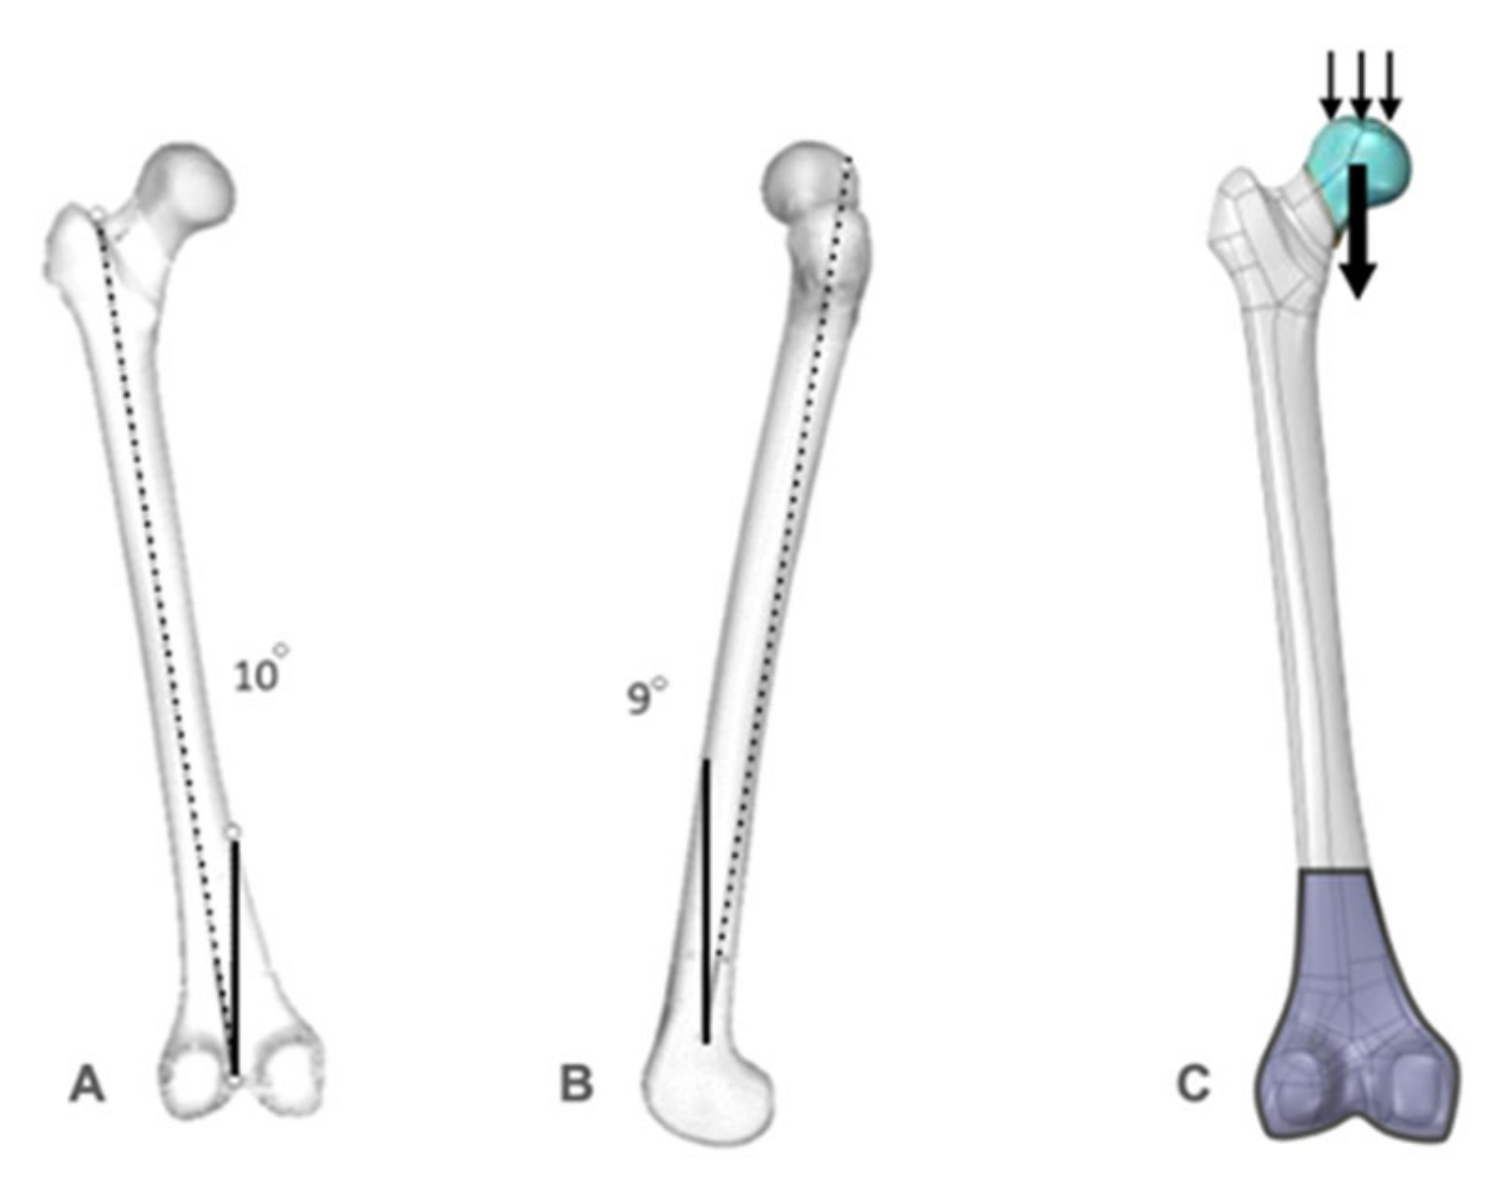

2. Materials and Methods